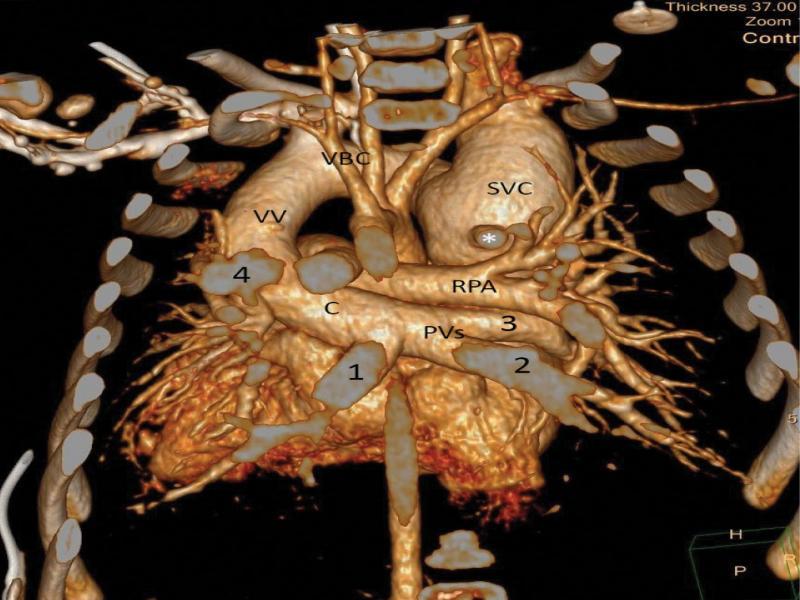

Angio-tomography 3-D reconstruction. The heart seen from the posterior perspective after removal of the vertebral column and posterior parts of the ribs. C: pulmonary vein confluence; PVs – pulmonary veins; 1 left lower, 2 – right lower, 3 – right upper. VV – vertical vein, VBC – left brachiocephalic vein, SVC – superior vena cava, * ostium of the azygos vein; RPA – right pulmonary artery. All vascular structures are clearly delineated on this picture. The only vein joining the superior caval vein has typical features of an azygos vein: runs in sagittal plane, does not receive any veins from the lungs